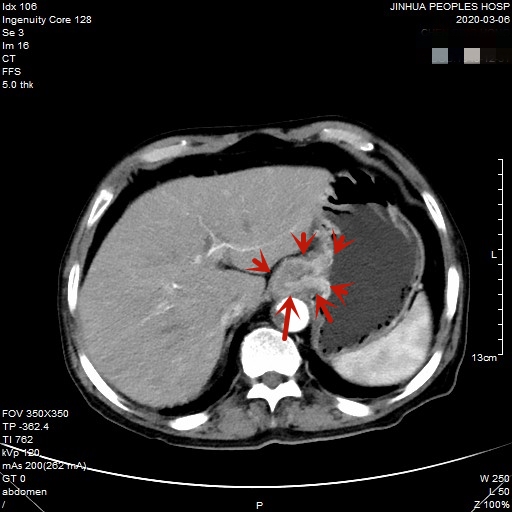

医生予以进一步检查CT增强发现肿瘤倒是没有明显侵犯周围脏器或结构,请我去会诊后,仔细阅片,发现从影像上看还是能够根治性切除的。所以转来胸外科拟进一步行手术治疗。下面是其CT增强的图像:

以上图片红色箭头所指处为贲门部肿瘤